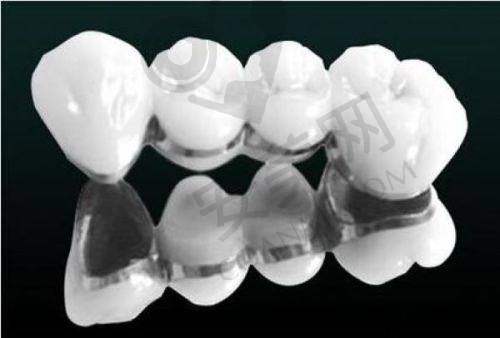

韩国登腾种植牙是一种常见的口腔种植系统。它采用了精良的技术和优质的材料,种植体的设计能够更好地与人体牙槽骨相结合。登腾种植牙的表面处理工艺有助于加快种植体与骨组织的愈合速度,提高种植的成功几率。其种植体的形状和规格多样,可以根据患者不同的口腔情况和需求进行选择。这种种植牙在国内外上也有广泛的应用,已经帮助了无数牙齿缺失患者修复了正常的咀嚼功能和美观。

首先,韩国登腾种植牙的成功几率较高。由于其精良的设计和表面处理技术,能够更好地与牙槽骨结合,减少了种植失败的风险。其次,它的使用寿命较长,一般可以使用多年甚至终身。再者,登腾种植牙的外观和功能都非常接近自然牙齿,能够修复患者正常的咀嚼功能和美观。另外,与传统的镶牙方式相比,种植牙更加舒适、方便,不会对相邻的牙齿造成损伤。